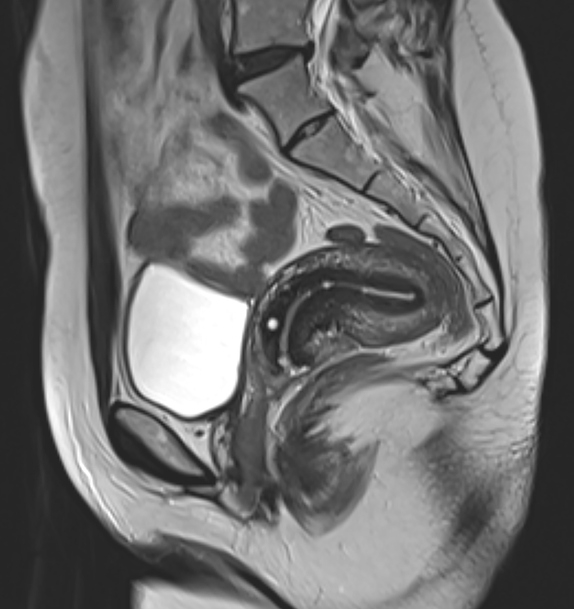

10.“I learned while I was pregnant with my oldest that I have a retroverted uterus, meaning my uterus is facing backward. It’s not super rare —it occurs in roughly 20% of women— but it certainly helped because I didn’t show until I was five months along with all three of my kids. Back labor is way worse, but the visible recovery was great… I was able to wear normal clothes almost immediately since everything was leaning back into my body.”